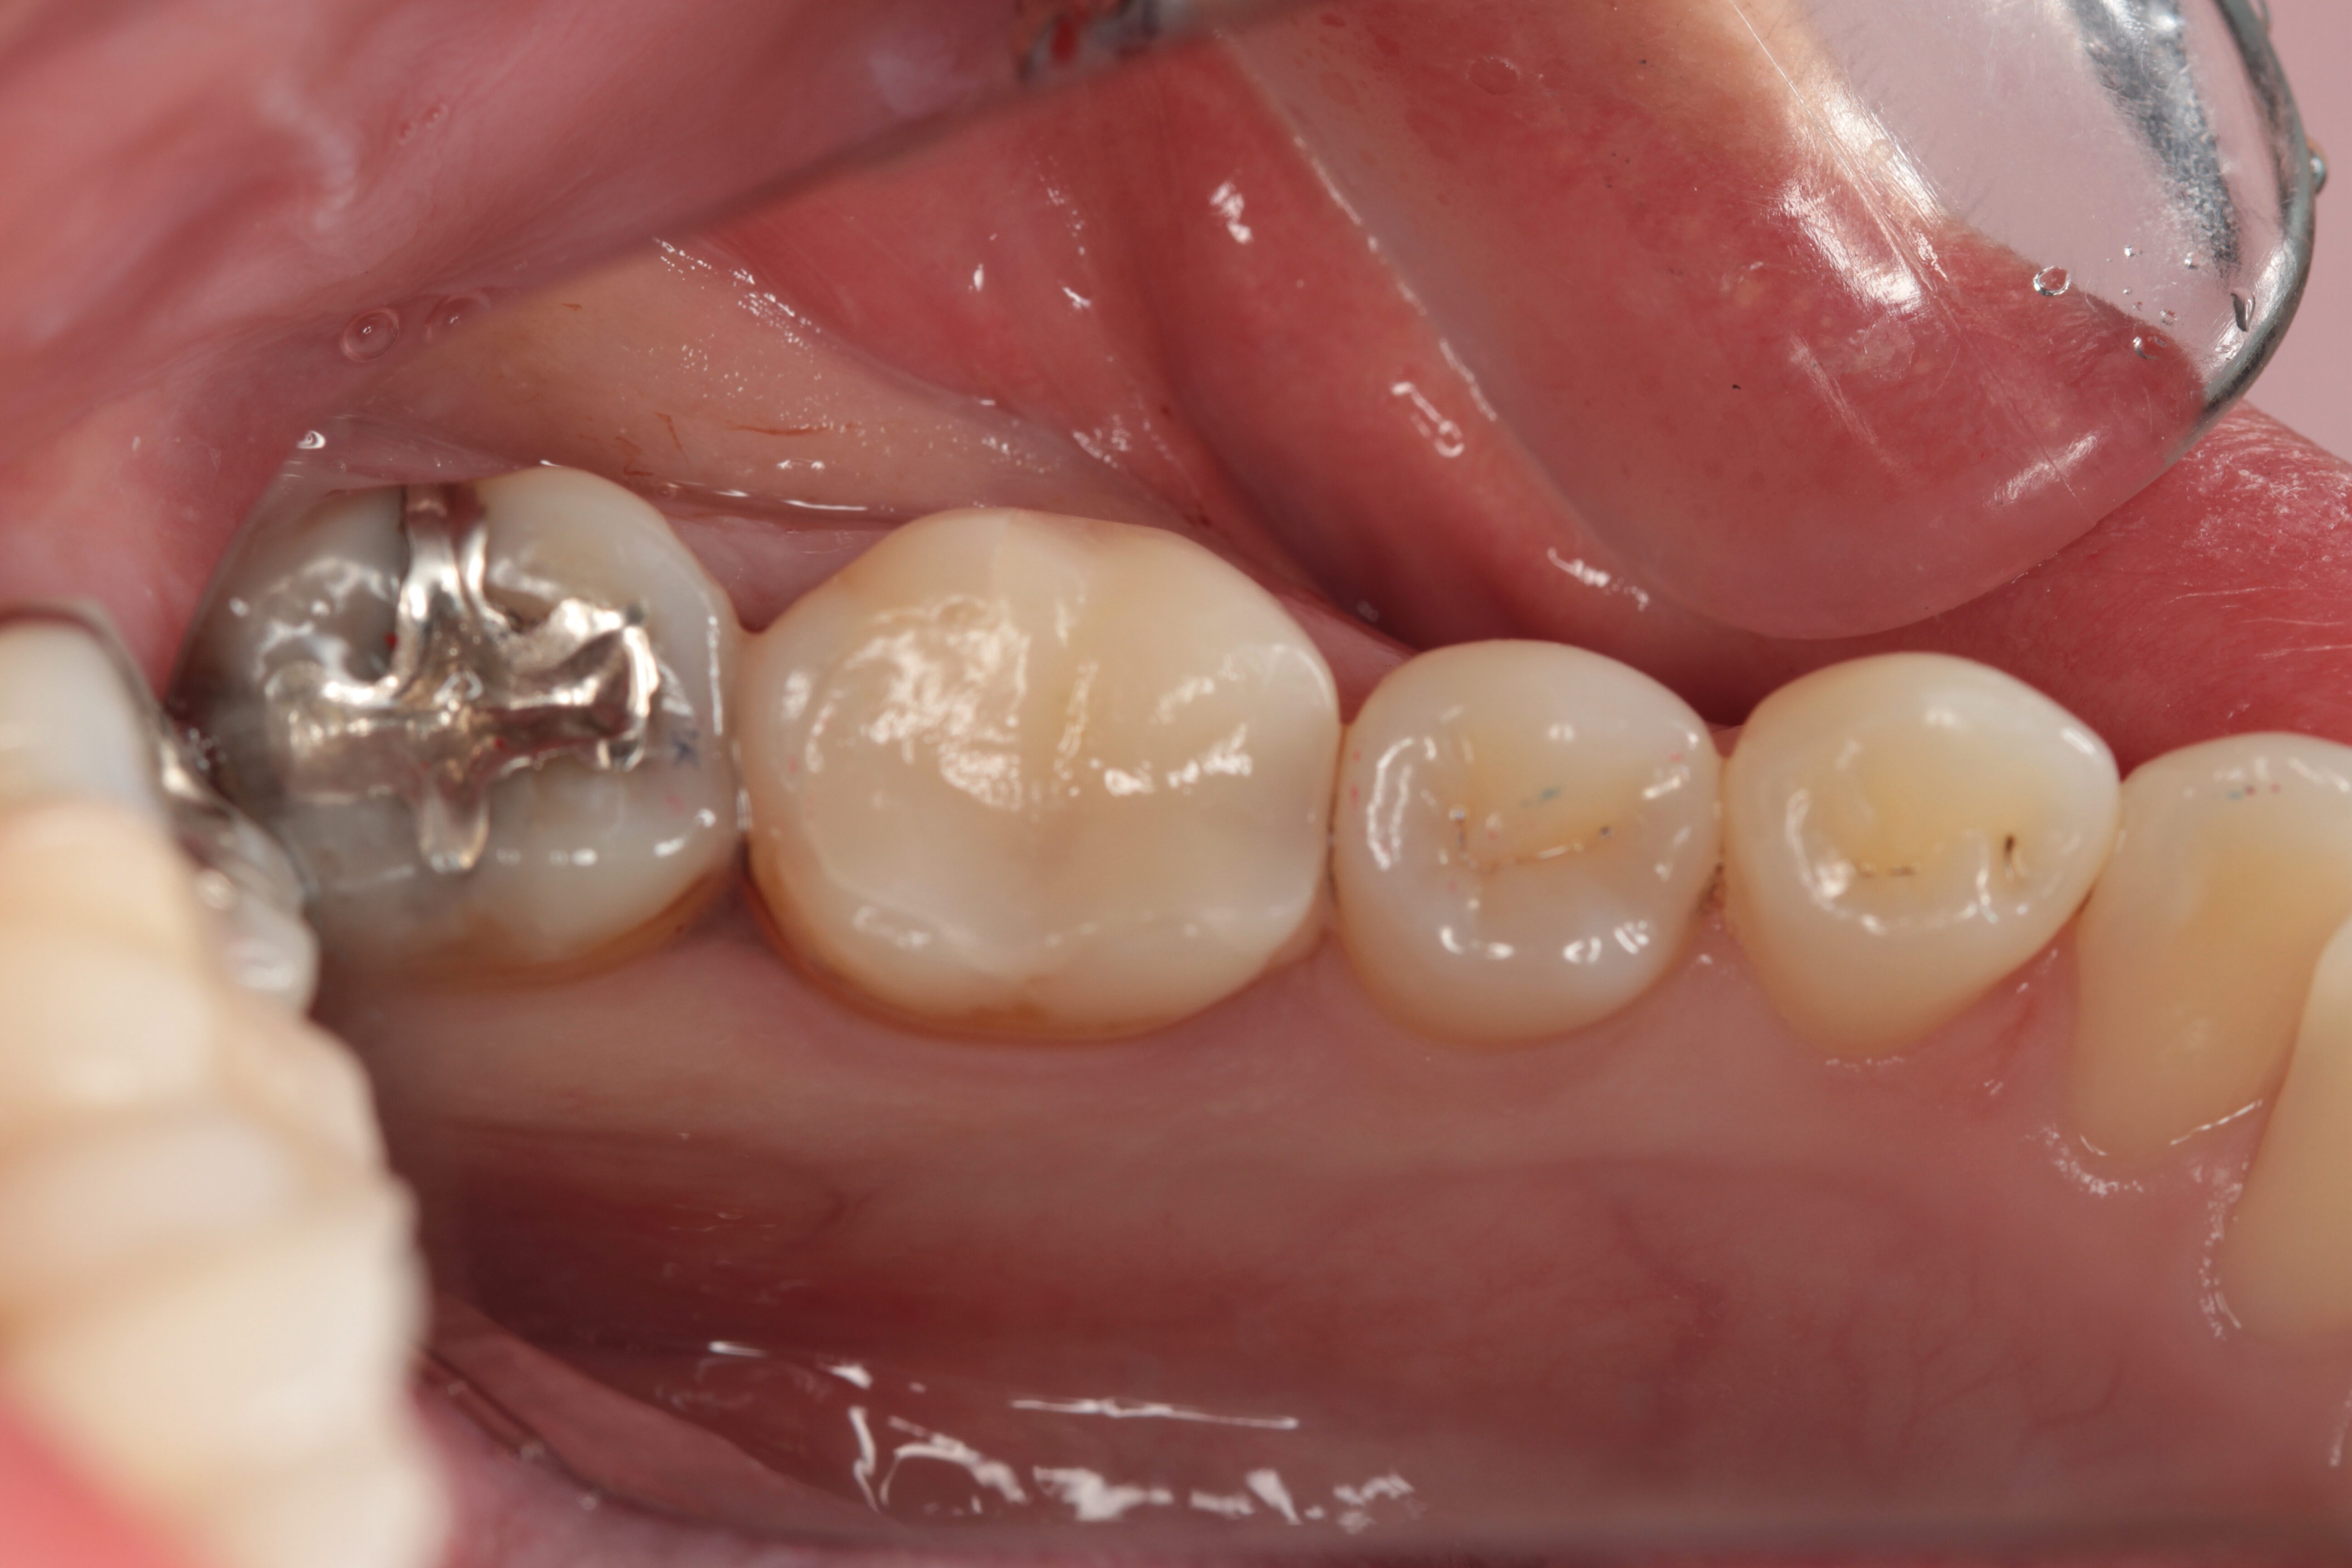

この症例は噛み合わせメインの治療で

噛めることの追求がメインテーマ。

それに付随してくるのは、自然なる美。

リスクとお話ししましたが、

セラミックは自分が壊れることで歯を守る。

衝突安全ボディです。

銀歯の方はぜひセラミックのご選択をしてください。